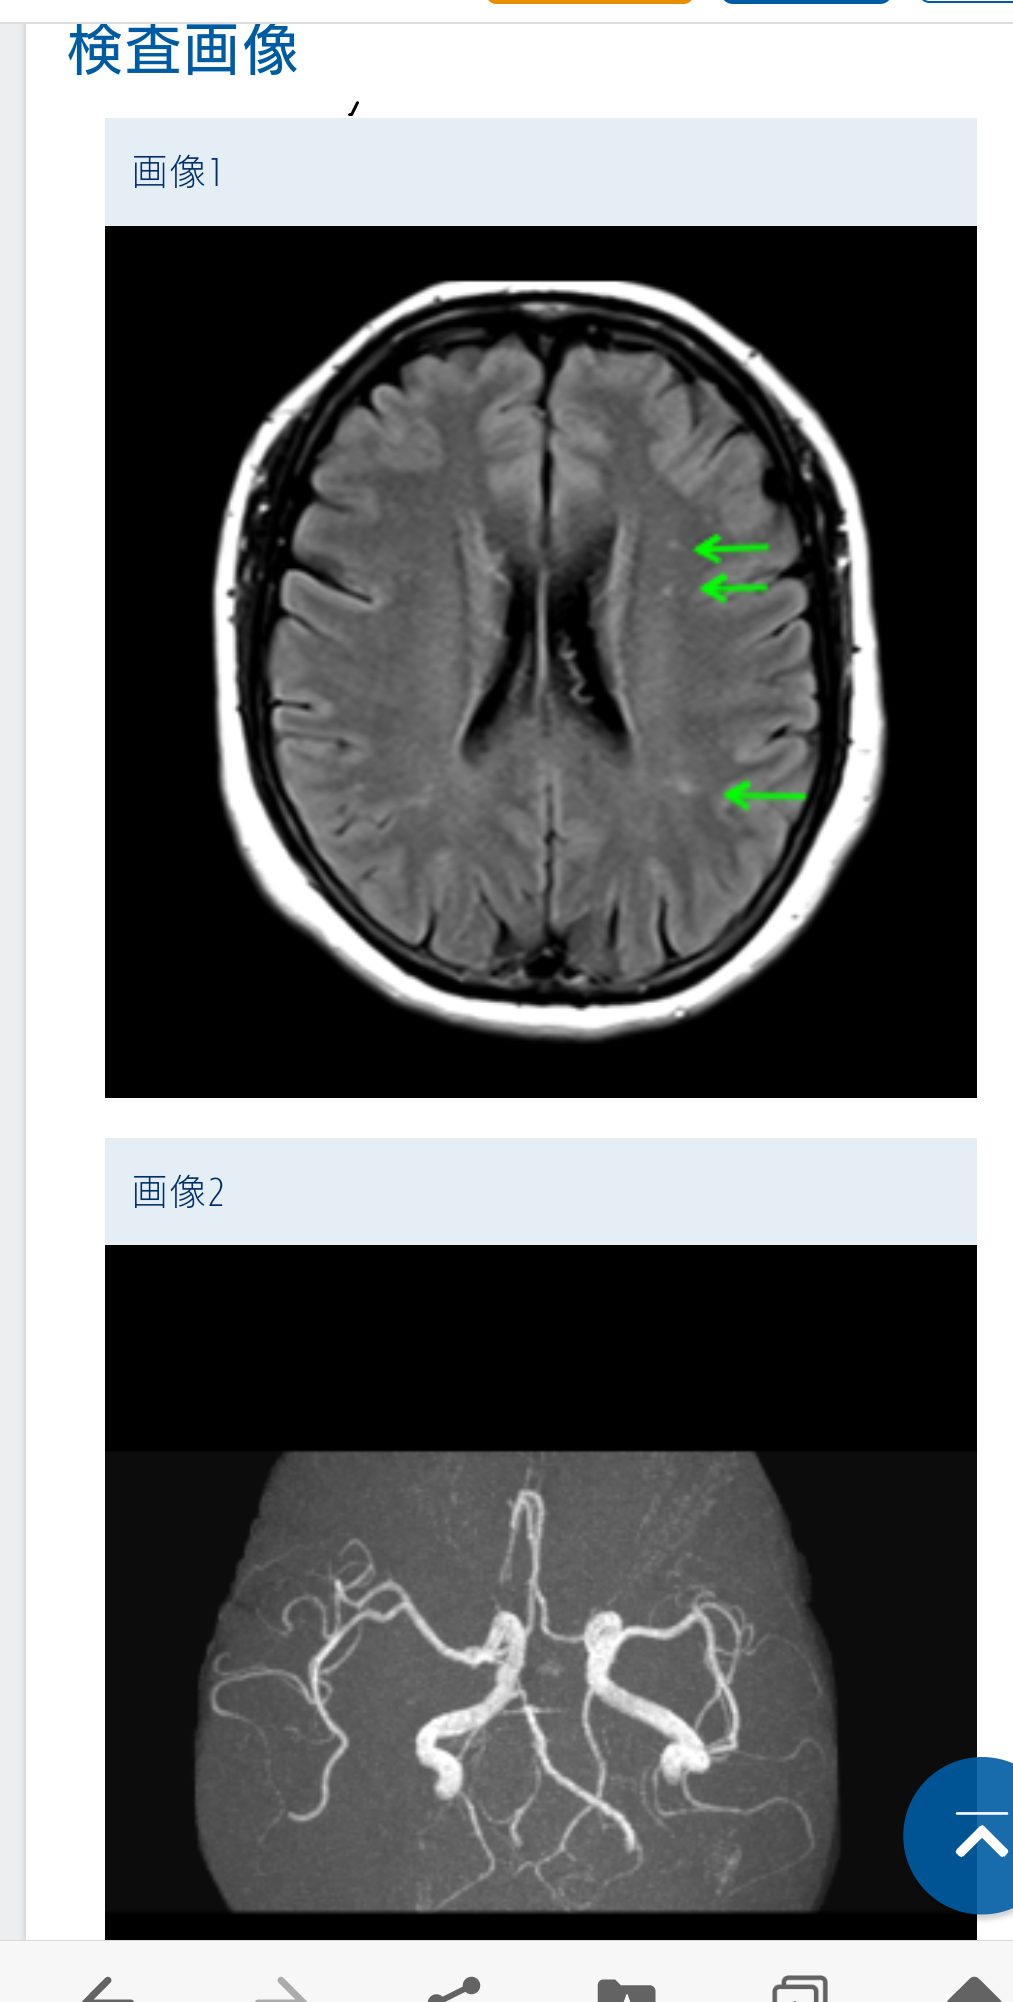

MRA所見で

動脈瘤 不整突出瘤 動脈解離

血管屈曲・蛇行 狭窄度 血管閉塞 脳血管奇形